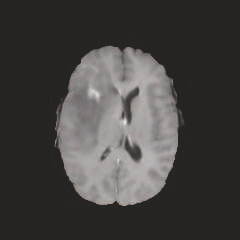

Multi-modal medical image completion has been extensively applied to alleviate the missing modality issue in a wealth of multi-modal diagnostic tasks. However, for most existing synthesis methods, their inferences of missing modalities can collapse into a deterministic mapping from the available ones, ignoring the uncertainties inherent in the cross-modal relationships. Here, we propose the Unified Multi-Modal Conditional Score-based Generative Model (UMM-CSGM) to take advantage of Score-based Generative Model (SGM) in modeling and stochastically sampling a target probability distribution, and further extend SGM to cross-modal conditional synthesis for various missing-modality configurations in a unified framework. Specifically, UMM-CSGM employs a novel multi-in multi-out Conditional Score Network (mm-CSN) to learn a comprehensive set of cross-modal conditional distributions via conditional diffusion and reverse generation in the complete modality space. In this way, the generation process can be accurately conditioned by all available information, and can fit all possible configurations of missing modalities in a single network. Experiments on BraTS19 dataset show that the UMM-CSGM can more reliably synthesize the heterogeneous enhancement and irregular area in tumor-induced lesions for any missing modalities.